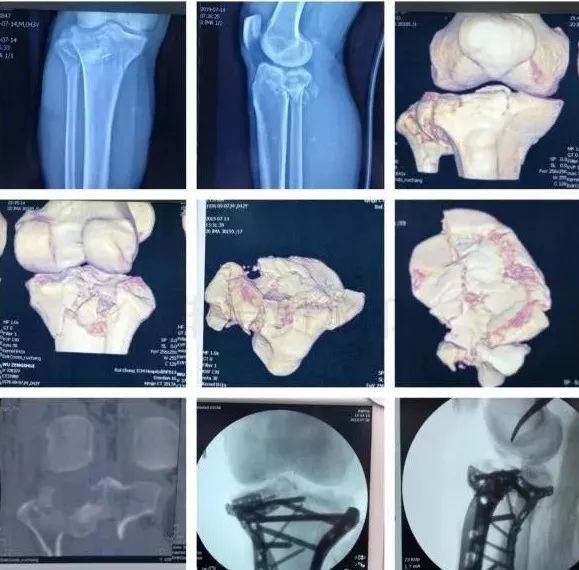

5)胫骨近端骨折(平台)

• 确定损伤机制,暴力损伤程度。

• 排除骨筋膜室综合征及血管,神经损伤。

图片

• 高能量损伤,皮肤软组织条件差的,应延期手术。